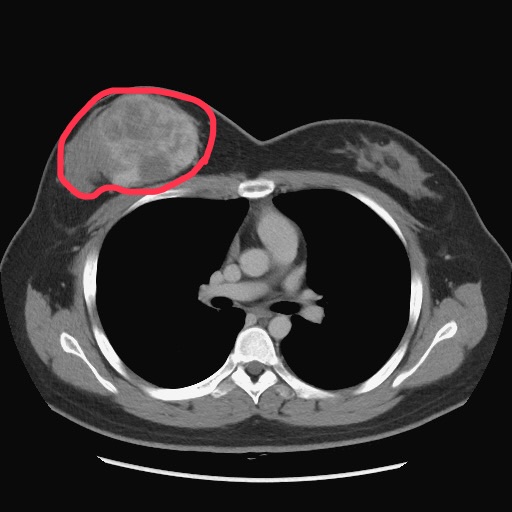

電腦斷層影像可見陳小姐右乳房的葉狀瘤(紅圈處)。(記者孫義方攝)

〔記者孫義方台中報導〕二十五歲的陳女去年初摸到右側乳房有硬塊,以為是生理週期的正常腫脹,不料,腫塊在兩週內快速長大讓胸部大了近一個罩杯。中榮乳房外科洪志強主任安排切片檢查確診為乳房葉狀瘤,因腫瘤已約九公分大且考量腫瘤周邊安全距離,右乳房須全切除。陳女說,當下腦筋空白,引以為傲的乳房須切除,切除後又意外發現懷孕,一想到孩子可能問「媽媽你的胸部為什麼跟別人不一樣!」讓她更確定重建決心。

乳房葉狀瘤發生率低,西方統計數據顯示,約占女性乳房腫瘤0.3-1%,好發於四十至五十歲女性,然任何年齡的女性都可能罹患葉狀瘤。葉狀瘤經切片組織型態病理分類為良性(占所有葉狀瘤50%以上)、邊緣性及惡性。標準治療方法是手術切除,不需要像一般乳癌般接受淋巴結切除、化學治療或放射線治療。陳女診斷為邊緣性葉狀瘤,因腫瘤大且為確保周邊組織安全距離,降低復發及轉移機率,故建議切除整個右乳房。